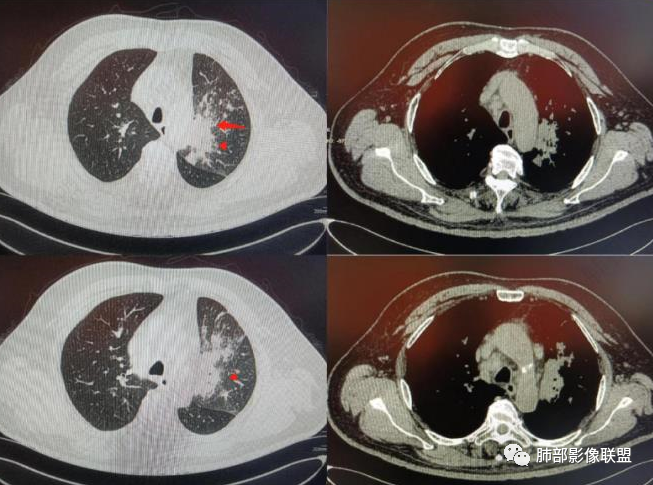

图1、2为同一病例,左肺下叶背段周围型肺Ca并左肺下叶局限型PLC,肿块与左下肺门间肺纹理不规则增粗,肿块与膈面有串珠样高密度影相连。图3为乳腺癌化疗后多发转移并弥漫型PLC,双肺多肺叶肺纹理不规则增粗增多并多发微小结节,其中右肺上叶后段肺纹理多呈典型的“毛刷征”,双肺上叶胸膜下区可见多发垂直于胸膜的不规则增厚的小叶间隔及微小结节。图4为右肺上叶周围型肺癌并弥漫型PLC,左肺上叶背段肺纹理不规则增粗增多呈典型的“毛刷征”,右侧叶间胸膜轻度增厚及多发微小结节。图5为胰腺癌术后多发转移并弥漫型PLC,双肺广泛肺纹理增多增粗并多发微小结节,双肺胸膜下多发肺小叶间隔增厚并见微小结节;图6(MPR冠状位)为食管癌术后肺弥漫型PLC,左肺广泛肺纹理不规则增多、增粗及多发小结节,边缘模糊。